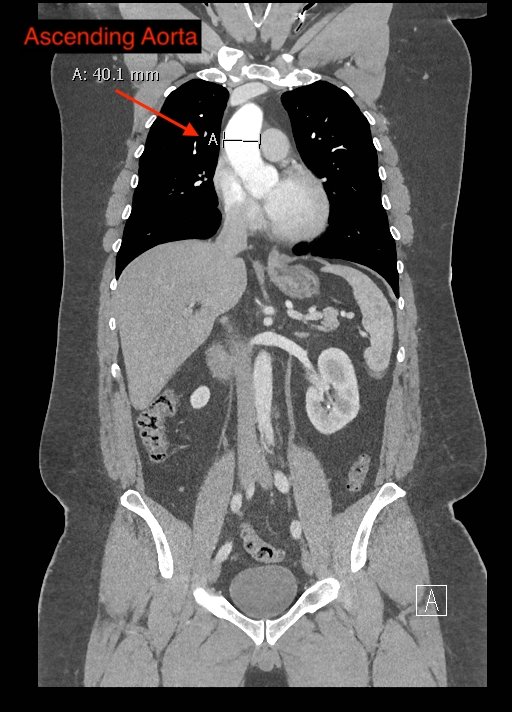

Point-of-care cardiac echocardiogram demonstrated a dilated ascending aorta (illustrated in red) measuring approximately 4 cm in the parasternal long axis (PLAX). A dilated aortic arch (illustrated in green) also measuring approximately 4 cm was appreciated using the suprasternal notch view (SSNV). A follow-up computed tomography angiogram (CTA) was performed, validating bedside ultrasound measurements.

The diagnostic criteria for dilated thoracic aneurysm is based on multiple factors including age, sex, and body size.2 An aortic root diameter of ³ 4.0 cm constitutes an ascending aortic dilation.3,4 Point-of-care cardiac and SSNV ultrasound of the thoracic aorta has been validated as an accurate study when performed by emergency physicians to identify thoracic aortic aneurysms (sensitivity of 71.4%, specificity of 100% when compared to gold standard of CTA). 5 This case is an example of the utility of rapid bedside diagnostic ultrasound, specifically the SSNV, in assessment of thoracic aneurysms.